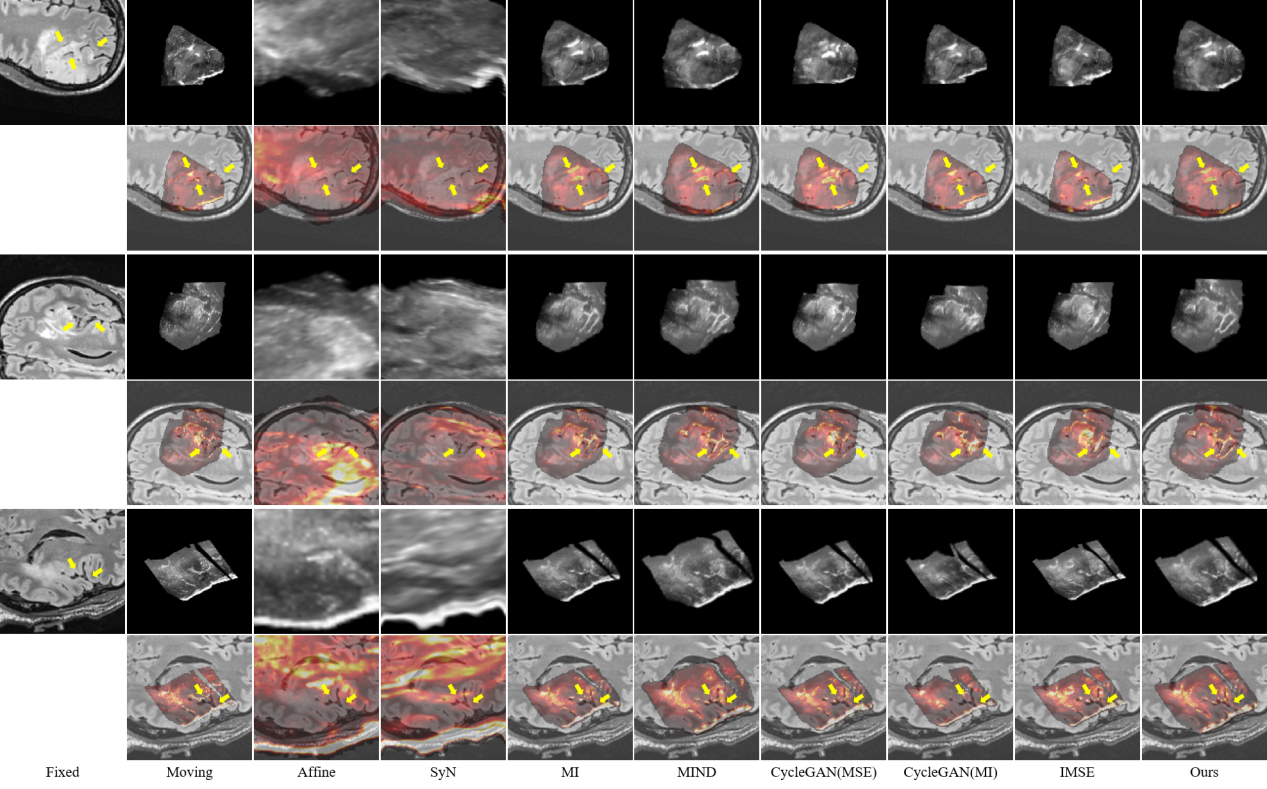

研究結(jié)果表明,SynMSE 在L2R 2022 CT-MR腹部數(shù)據(jù)集、臨床宮頸CT-MR數(shù)據(jù)集以及CuRIOUS MR-US腦數(shù)據(jù)集上均取得了最優(yōu)配準(zhǔn)性能。與傳統(tǒng)方法相比,SynMSE顯著提升了Dice系數(shù)、降低了HD95與TRE誤差,實(shí)現(xiàn)了在復(fù)雜模態(tài)差異下的高精度解剖結(jié)構(gòu)對齊。圖4-圖6分別為所提出方法在三個數(shù)據(jù)集上的定性結(jié)果展示,紅色標(biāo)注代表固定圖像的目標(biāo)器官區(qū)域,黃色標(biāo)注代表浮動圖像與配準(zhǔn)后圖像的目標(biāo)器官區(qū)域。表示圖中結(jié)果顯示,SynMSE更好的克服了多模態(tài)圖像間的復(fù)雜分布差異,不僅實(shí)現(xiàn)了更精確的配準(zhǔn)效果,而且有效保持了組織邊界與解剖拓?fù)涞耐暾裕黠@優(yōu)于現(xiàn)有方法。

圖6:所提出方法與現(xiàn)有方法在CuRIOUS MR-US腦數(shù)據(jù)集上的定性效果(黃色箭頭指向圖像上的較為明顯的腦溝等顯著結(jié)構(gòu))